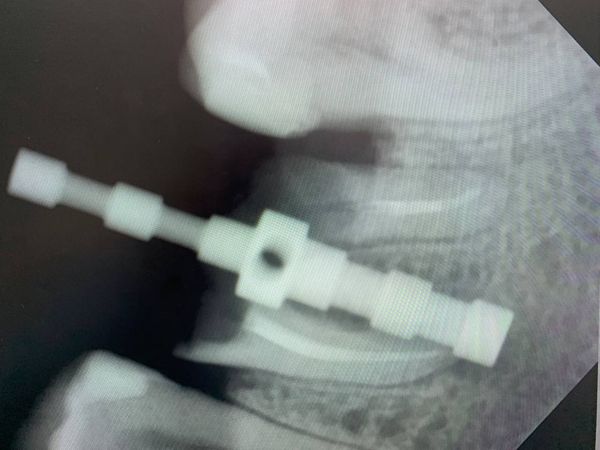

- установили дентальный имплант размером 4,3×10 мм фирмы SNUCONE в межкорневую перегородку;